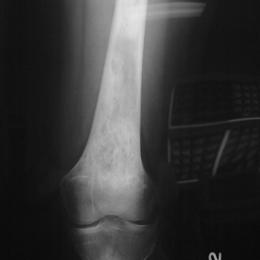

Radiographic imaging is used to help form a diagnosis. These include X-Ray, MRI, CT and Bone Scans.

An example of an X-Ray is shown.